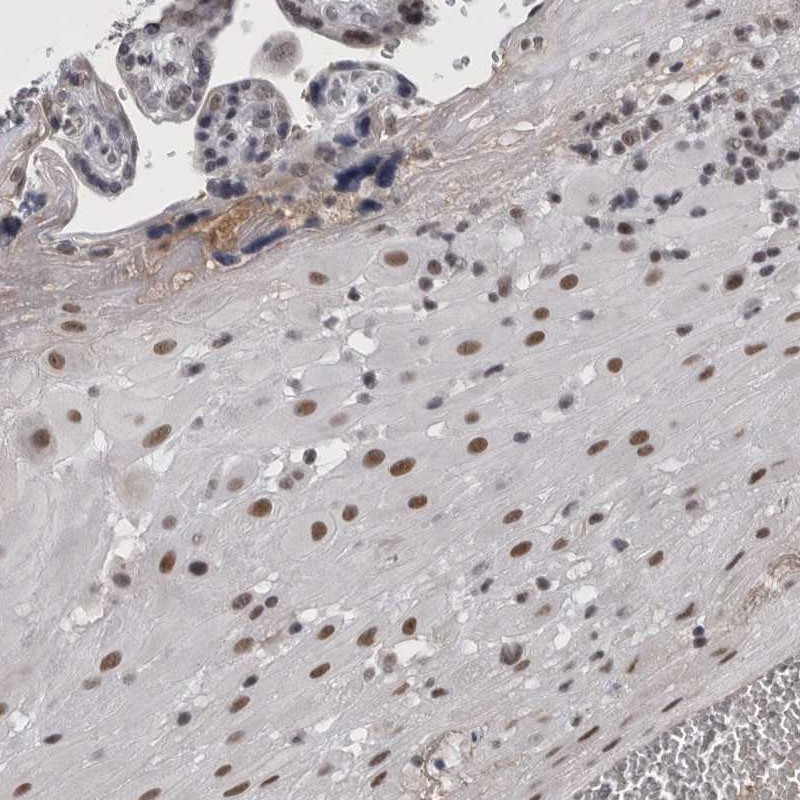

Immunohistochemical staining of human placenta shows moderate nuclear positivity in decidual cells.